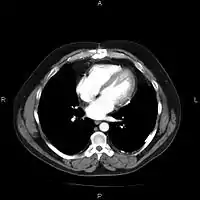

An image as stored on a picture archiving and communication system (PACS)